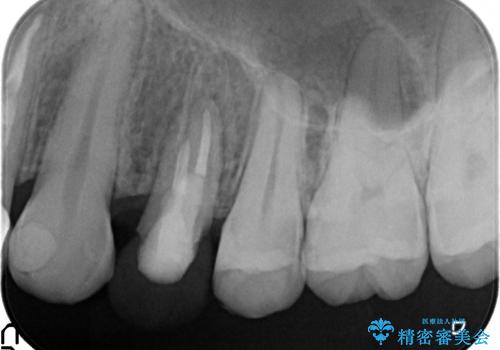

左上4の補綴物を除去したところ縁下歯質だったため、歯牙の挺出を提案し行いました。

挺出終了後は歯肉切除および骨外科により歯周組織を整え、オールセラミッククラウンによる補綴を行いました。